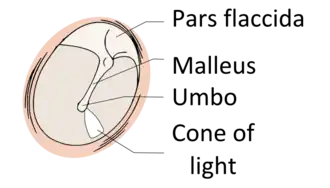

Regions

The eardrum is divided into two general regions: the pars flaccida and the pars tensa.[3] The relatively fragile pars flaccida lies above the lateral process of the malleus between the Notch of Rivinus and the anterior and posterior malleal folds. Consisting of two layers and appearing slightly pinkish in hue, it is associated with Eustachian tube dysfunction and cholesteatomas.[4]

The larger pars tensa consists of three layers: skin, fibrous tissue, and mucosa. Its thick periphery forms a fibrocartilaginous ring called the annulus tympanicus or Gerlach's ligament.[5] while the central umbo tents inward at the level of the tip of malleus. The middle fibrous layer, containing radial, circular, and parabolic fibers, encloses the handle of malleus. Though comparatively robust, the pars tensa is the region more commonly associated with perforations.[6]

Umbo

The manubrium (Latin for "handle") of the malleus is firmly attached to the medial surface of the membrane as far as its center, drawing it toward the tympanic cavity. The lateral surface of the membrane is thus concave. The most depressed aspect of this concavity is termed the umbo (Latin for "shield boss").[7]

When the eardrum is illuminated during a medical examination, a cone of light radiates from the tip of the malleus to the periphery in the anteroinferior quadrant, this is what is known clinically as 5 o'clock.